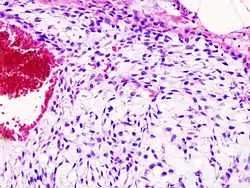

Histopathology